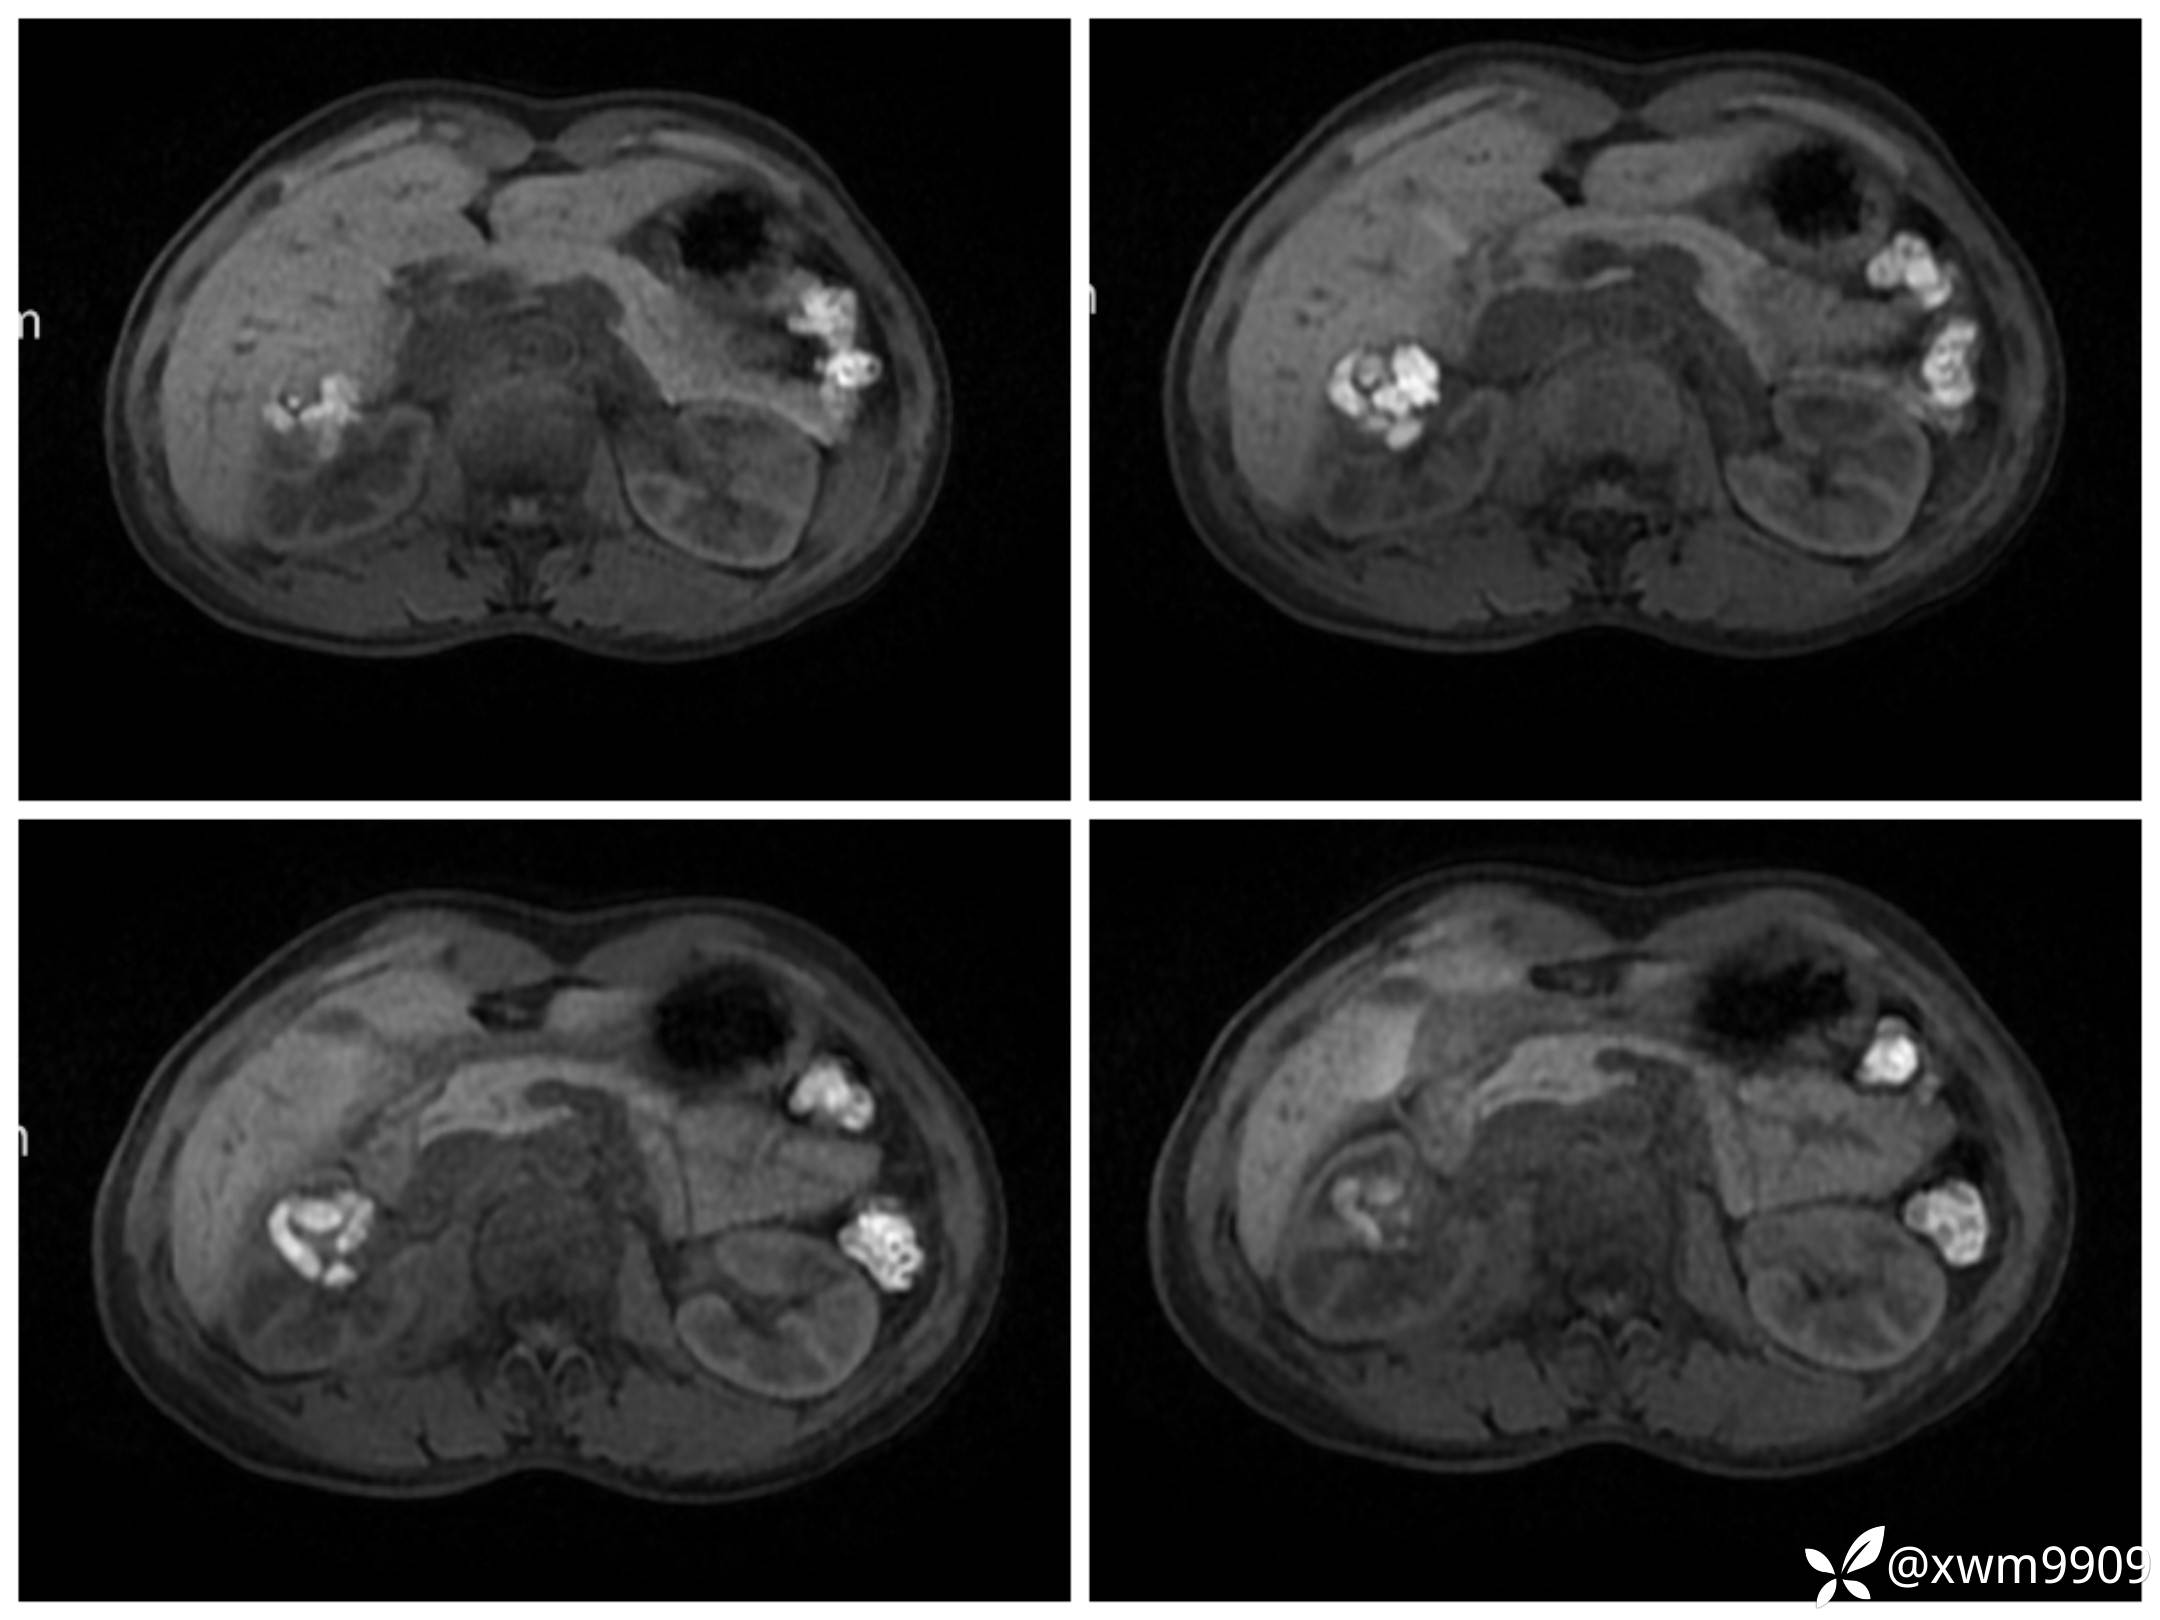

A:

v:

平衡期:

DwI丶ADC: